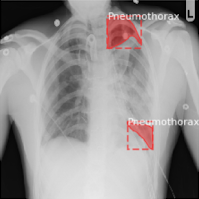

Leveraged Deep Learning Computer Vision models to detect Pneumonia in X-Ray imagery, using both fine-tuning of existing Computer Vision models from PyTorch, as well as Convolutional Neural Network